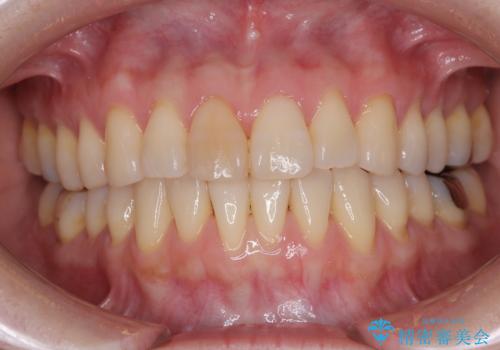

[マルチブラケットで後方移動] ワイヤー矯正で行う噛み合わせの改善